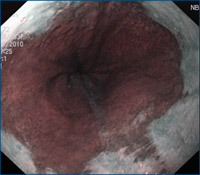

Magenspiegelung mit Kontrastverstärkung im Bereich der unteren Speiseröhre bei Verdacht auf Barrett-Syndrom mit Narrow Band Imaging (NBI). Durch einen speziellen Filter kann die Kontrastierung bei der Betrachtung im Bereich der unteren Speiseröhre so angehoben werden, dass geringe Veränderung der Schleimhaut in der Endoskopie erkannt und durch gezielte Gewebeprobenentnahmen weiter differenziert werden können.